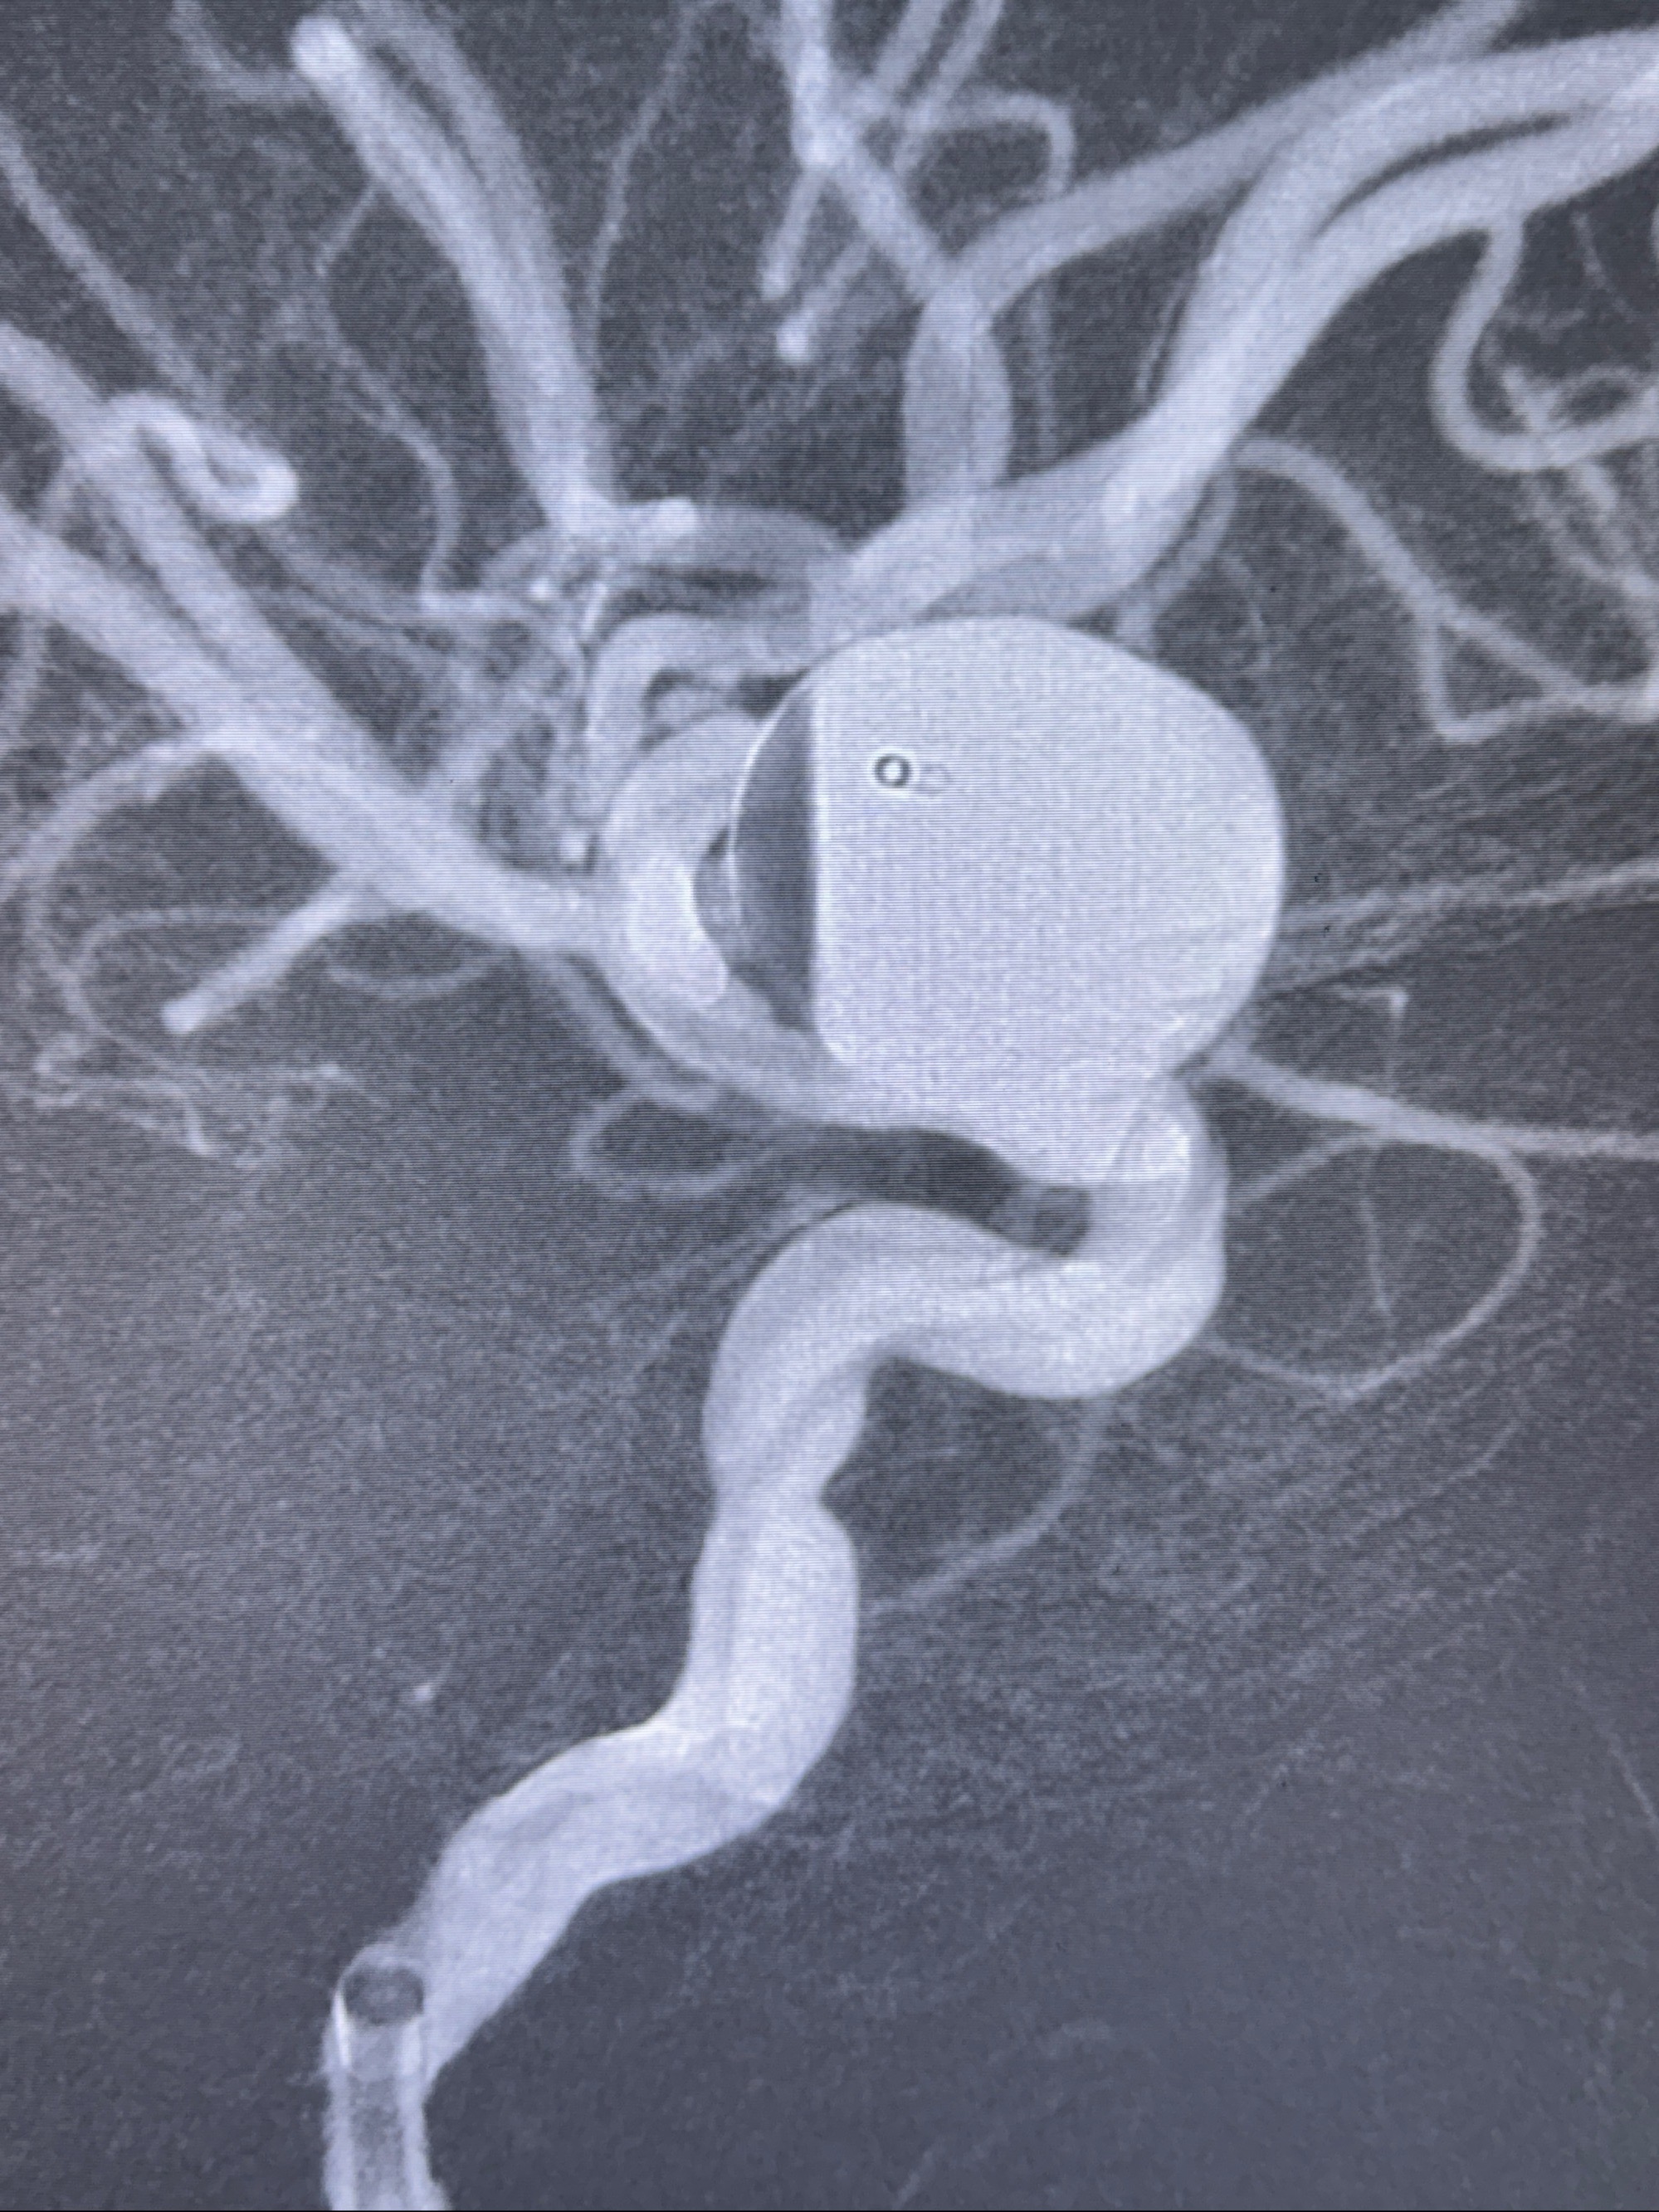

依次选取支架远段释放角度、动脉瘤近心段支架释放角度及瘤颈部切线位置

旋转3D展示动脉瘤局部的血管构筑

测量动脉瘤的大小:16*13.8*7.6mm大小,较原先变大,考虑双抗后瘤内血栓溶解可能

多角度显示支架打开情况

造影显示支架贴壁情况